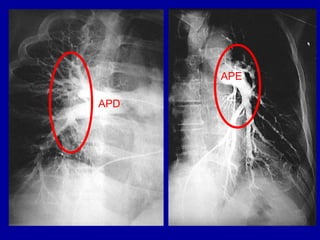

HILOS PULMONARES

• QUAIS ESTRUTURAS COMPÕEM OS HILOS

PULMONARES?

– VASOS PULMONARES

– BRÔNQUIOS

– LINFONODOS E VASOS LINFÁTICOS

APD

APE

HILOS PULMONARES:

ESQUERDO MAIS

ALTO QUE

DIREITO